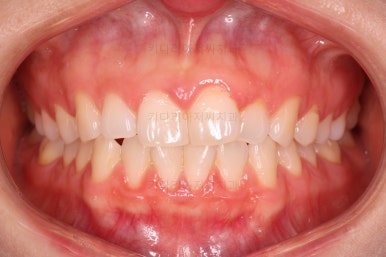

장치 부착 시점의 사진입니다.

장치를 붙이고 철사가 구불구불 들어가게 되면 그제서야 "이렇게 많이 틀어져 있었구나"를 더 잘 느 끼시게 됩니다.

이번에 사용한 장치는 엠파워 클리어라고 하는 자가결찰 세라믹 장치인데 같은 계열로는 엠파워 클리어를 비롯해 클리피씨 등이 있어요.

치아에 붙는 장치가 치아색과 비슷한 세라믹으로 만들어져 있고 철사를 붙잡아 주는 클립이 달려 있어 스스로 철사를 묶을 수 있다고 해서 "자가결차" 이라고 표현해요.

클리피씨 장치가 가장 유명하긴 하지만 매우 다양한 제품이 있고 거의 비슷한 장치이기 때문에 의사와 상의 하에 선택을 하시면 됩니다.

엠파워 장치는 미국, 클리피씨는 일본장치이며 기능적으로는 둘 다 우수한 장치입니다.